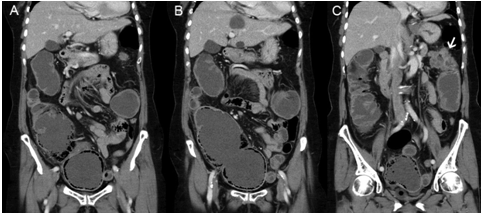

A 73-year-old diabetic female was presented to the emergency department with lower abdominal pain and distension for five days. Physical examination revealed tenderness over her right iliac fossa and supra-pubic region. An abdominal X-ray (Figure 1) revealed a spherical structure in the pelvis in the expected position of the bladder with presence of intramural gas and a provisional diagnosis of emphysematous cystitis was made by the emergency physicians. Urinary catheterization performed yielded clear urine and urine dipstick did not reveal any evidence of urinary tract infection. The patient's abdominal pain and distension worsened and a surgical consult was made. Further history corroborated with the patient's family revealed that the patient has had associated absolute constipation for last five days. The abdominal X-ray was reviewed which also showed a loop of dilated transverse colon. There was suspicion of colonic intestinal obstruction. Computed tomography (CT) scan of her abdomen and pelvis (Figure 2) showed a massively dilated cecum extending into the pelvis with evidence of pneumatosis intestinalis secondary to a closed loop obstruction from a stenotic splenic flexure colonic tumor. The patient underwent an exploratory laparotomy which revealed a large circumferential and stenotic splenic flexure tumor causing resultant proximal large bowel obstruction. The cecum was massively dilated measuring up to 14 cm in diameter and the cecal wall appeared thinned out and dusky. The ascending and transverse colon were also dilated up to 5 cm in diameter but still appeared healthy. The patient underwent a subtotal colectomy and was discharged well on postoperative day-10. Histopathological examination of the resected colon revealed a moderately differentiated adenocarcinoma of the splenic flexure exhibiting transmural invasion with involvement of the serosa and omental fat. There was no malignancy identified in 28 harvested lymph nodes and resection margins were free of tumor. The cecum demonstrated mural attenuation with mucosal ulceration and a small focal perforation. The histopathological findings corresponded to a provisional tumor node metastasis (TNM) staging of T4N0.

Figure 1: Plain supine abdominal X-ray of the patient showing a circular radiolucent rim (as indicated by the arrow) at the expected position of the bladder in the pelvis suggestive of emphysematous cystitis.

Emphysematous cystitis is a rare but potentially life-threatening clinical entity where there is presence of gas within the bladder wall and lumen during a urinary tract infection. It usually occurs in elderly women with poorly controlled diabetes mellitus [1] [2] [3]. Common causative pathogens are gas forming organisms like Escherichia coli and Klebsiella pneumoniae [4]. Patients with emphysematous cystitis frequently present with symptoms of abdominal pain, gross hematuria and fever but a significant proportion of patients can be asymptomatic with diagnosis of emphysematous cystitis made incidentally on abdominal imaging [5]. Intra-mural gas can be seen on plain abdominal or pelvic X-rays as curvilinear or circular areas of increased radiolucency in the expected position of the bladder and intra-luminal gas can be seen as an air-fluid level. In our patient, the abdominal X-ray revealed a circular radiolucent rim centrally located within the pelvis which was highly suggestive of emphysematous cystitis. Although she presented with lower abdominal pain, she did not have any other symptoms of cystitis such has hematuria, dysuria, urinary frequency or urgency. Urine dipstick analysis of the urine also did not reveal any evidence of urinary tract infection such as the presence of leucocytes or nitrites. In view of the discordance between her presenting symptoms, urine dipstick analysis and X-ray findings, a CT scan was subsequently performed which revealed that the rim of gas in the pelvis was actually pneumatosis intestinalis of the cecum. The cecum was massively dilated and directed into the pelvis secondary to a closed loop obstruction from a stenotic transverse colon tumor and competent ileocecal valve. We hypothesize that apart from pneumatosis intestinalis of the cecum, pneumatosis intestinalis of the sigmoid colon and rectum could also possibly mimic the X-ray findings of emphysematous cystitis. The subsequent management and disposition of a patient with pneumatosis intestinalis of the colon or rectum will differ significantly with that of emphysematous cystitis.